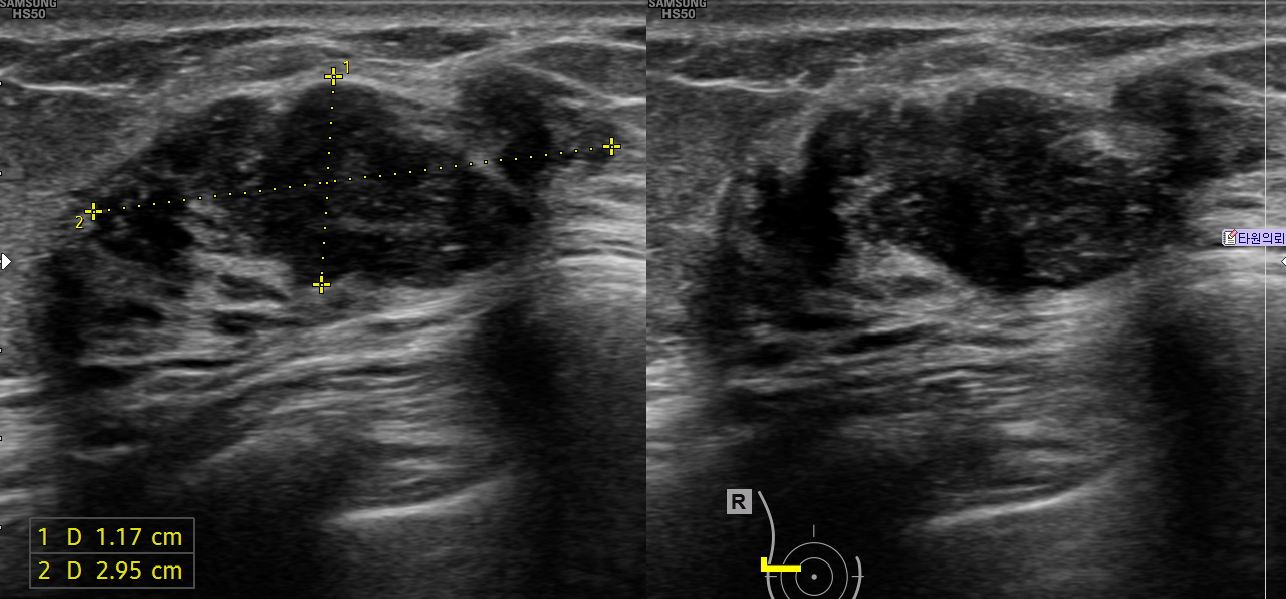

아산유외과 개원후 624번째 유방암 진단

상기 환자 외부검사상 이상소견으로 내원하신 60대 여성으로 우측에 의심스러운혹있어 조직검사 시행후 유방암 진단되었습니다.